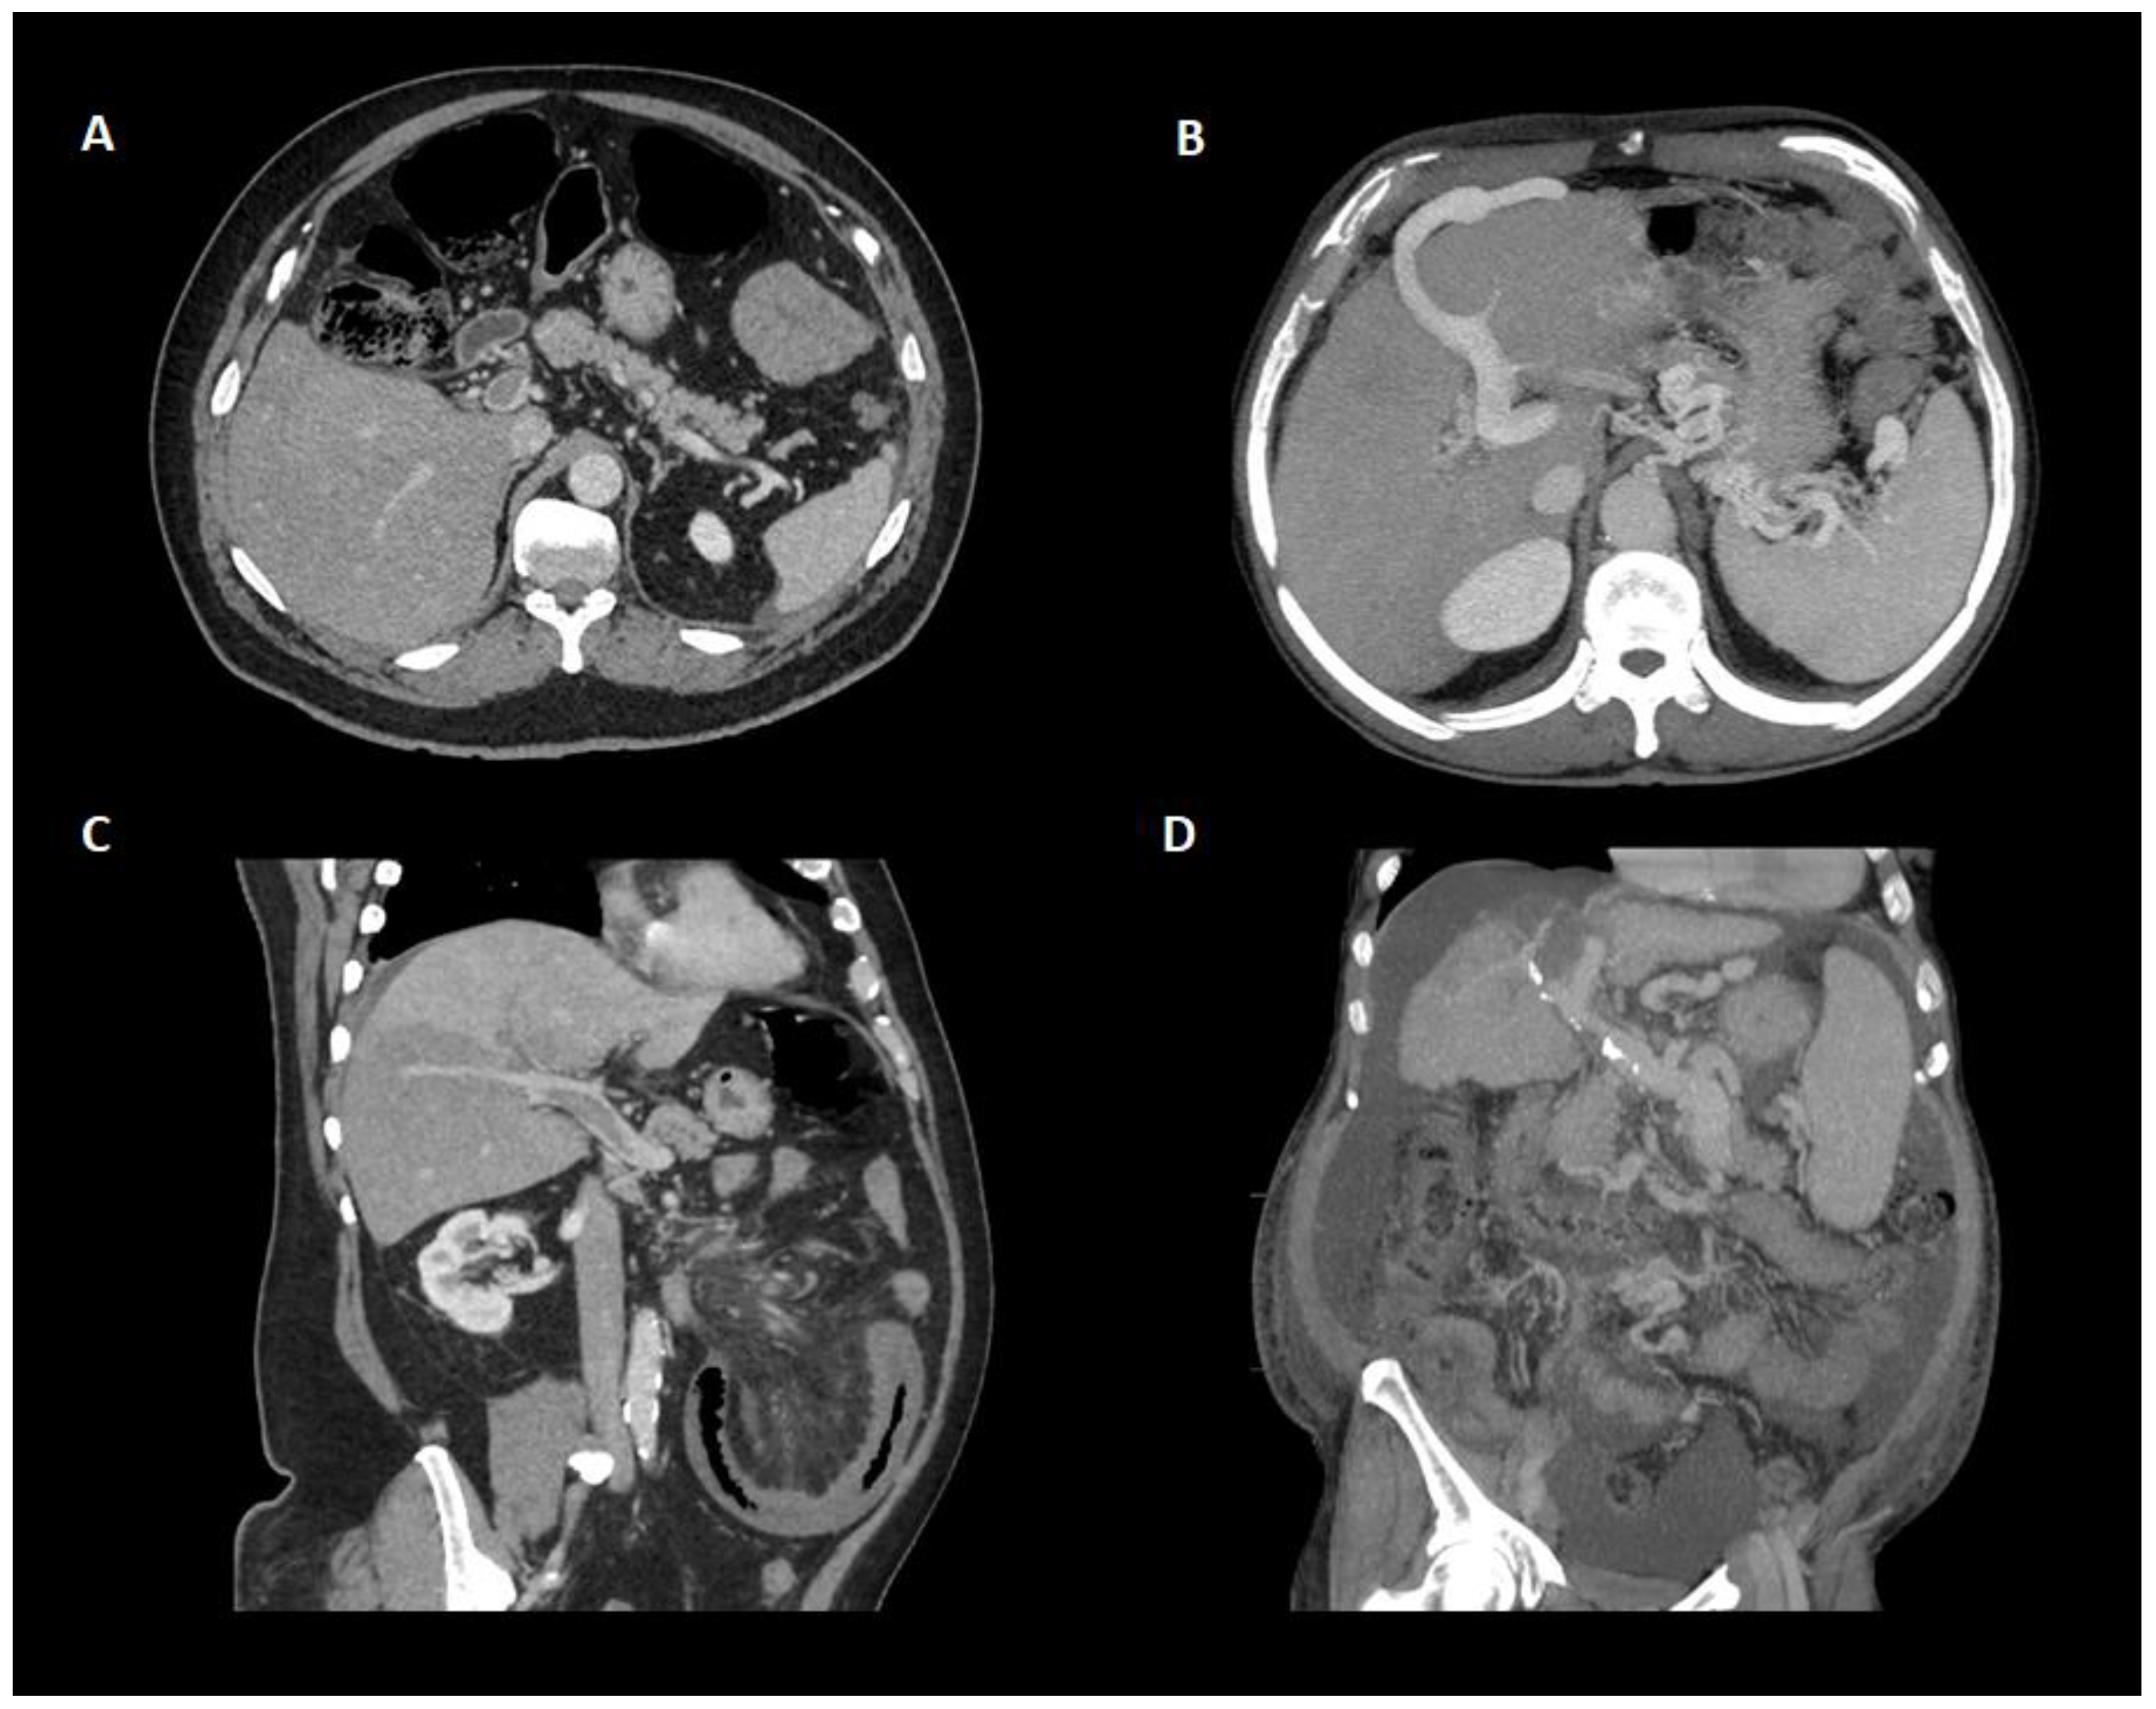

Figure 3.

Different presentations of portal vein thrombosis through contrast-enhanced CT scan. (A) Axial plane showing a partially occlusive portal vein thrombosis of the main portal trunk without collaterals or other indirect signs of portal hypertension. (B) Apparition of collateral circulation with umbilical vein repermeabilization and enlarged spleen in the context of portal vein thrombosis. (C) Oblique plane showing a partially occlusive portal vein thrombosis of the main portal trunk with hepatic perfusion defects on the lower segments of the right lobe. (D) Chronic portal vein thrombosis in patient with cirrhosis. Note the calcification of the portal vein as an indirect sign of chronicity. Atrophic liver with splenomegaly, collaterals, and ascites are found in the context of cirrhosis.